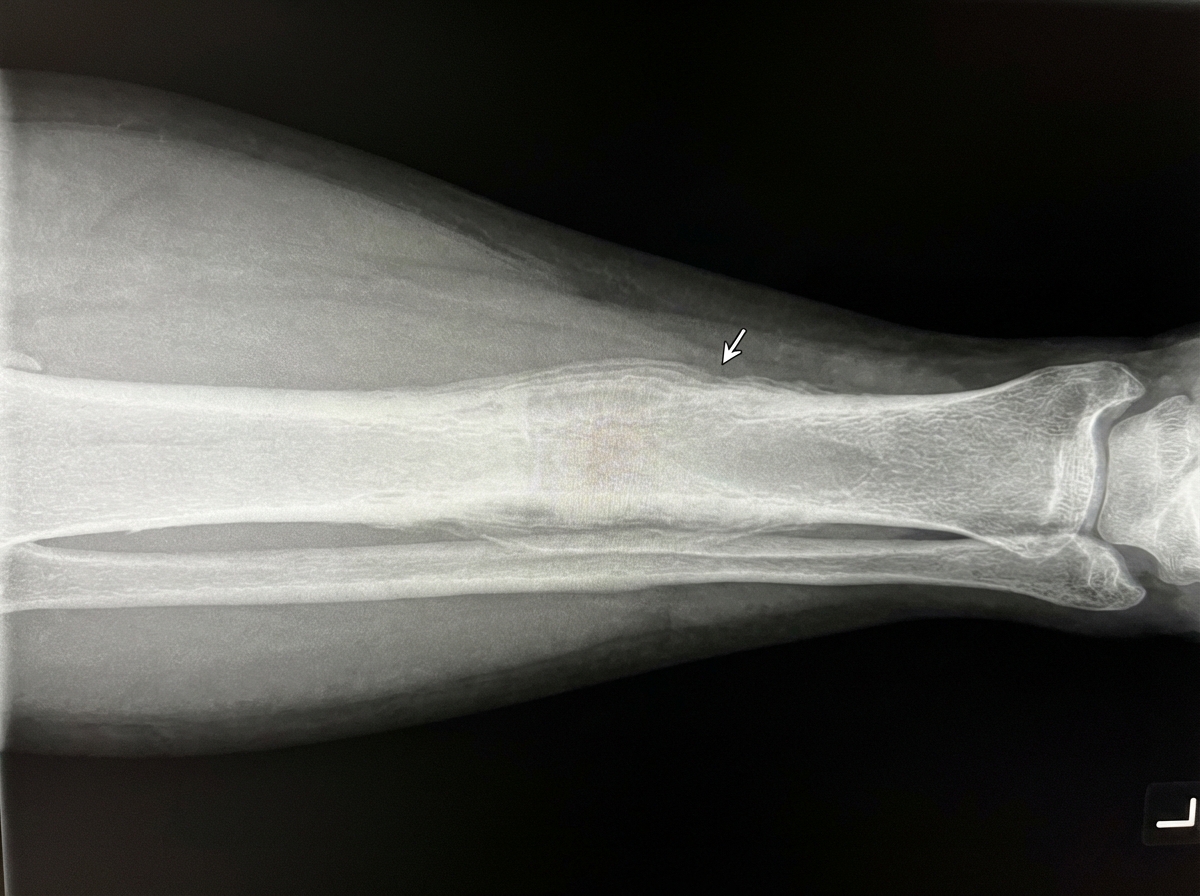

The most likely pathology associated with the following radiograph is:

Explanation: ***Garre's osteomyelitis*** - Characterized by **dense sclerosis**, **cortical thickening**, and prominent **periosteal reaction** without evidence of **sequestrum formation** or pus collection. - Also known as **sclerosing non-suppurative osteomyelitis**, it presents with characteristic **onion-peel** periosteal layering and absence of bone destruction. *Chronic suppurative (or rarefying) osteomyelitis* - Shows **bone destruction** with **sequestrum formation** and **involucrum** development, which are absent in this case. - Typically demonstrates **lytic lesions** with areas of bone necrosis and pus formation. *Acute osteomyelitis* - Presents with **bone marrow edema**, **soft tissue swelling**, and early **osteolytic changes** without significant sclerosis. - Lacks the characteristic **dense sclerotic reaction** and organized periosteal response seen here. *Sclerosing osteomyelitis* - This is a **broader category** that encompasses various sclerotic bone infections including Garre's osteomyelitis. - **Garre's osteomyelitis** is a specific subtype within sclerosing osteomyelitis, making it the more precise diagnosis in the Indian PG context.